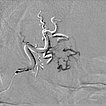

After super-selective catheterization via a microcatheter, stepwise filling of the entire nidus of the AVM using ethylene-vinyl alcohol copolymer with plug-and-push technique, in which the catheter tip is glued in place and the embolic agent is pressed into the lesion. Image in roadmap technique shows previously injected embolic agent in white and newly injected embolic agent in black. Note the increasing retrograde filling of the small feeder artery at the bottom of the lesion (start of injection).

Note the increasing retrograde filling of the small feeder artery at the inferior border of the lesion (during injection).

Note the increasing retrograde filling of the small feeder artery at the bottom of the lesion (after injection). The small artery was retrogradely filled against its flow direction.